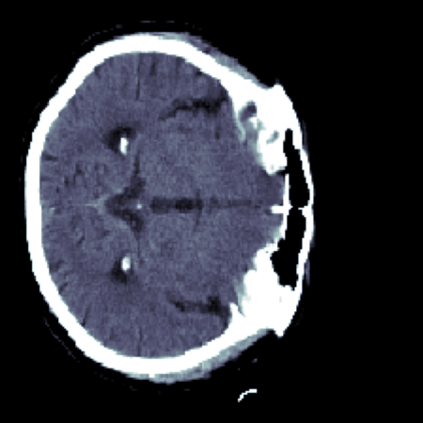

The sigmoid activation is the standard output activation function in binary classification and segmentation with neural networks. Still, there exist a variety of other potential output activation functions, which may lead to improved results in medical image segmentation. In this work, we consider how the asymptotic behavior of different output activation and loss functions affects the prediction probabilities and the corresponding segmentation errors. For cross entropy, we show that a faster rate of change of the activation function correlates with better predictions, while a slower rate of change can improve the calibration of probabilities. For dice loss, we found that the arctangent activation function is superior to the sigmoid function. Furthermore, we provide a test space for arbitrary output activation functions in the area of medical image segmentation. We tested seven activation functions in combination with three loss functions on four different medical image segmentation tasks to provide a classification of which function is best suited in this application scenario.